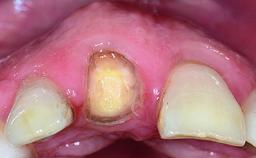

Replacement of a Failing Upper Left Central Incisor: Immediate Placement of an RC Bone Level Implant and Provisionalization

A healthy 23-year-old female patient was referred for a consultation on replacing tooth 21 with an implant-supported restoration. The patient had recently moved to the area and reported a history of endodontic and periodontal treatment for tooth 21. The tooth had been deemed non-restorable by her previous periodontist but since she was going to be moving, he recommended consulting to a dentist in her new city to continue her treatment. A review of her medical history yielded no significant findings and no known drug allergies. The analysis of her smile revealed a medium to high symmetrical smile line and a slightly discolored tooth 21.

Provisional Implant-Supported Prosthesis Prosthodontic margin < 3 mm apical to mucosal margin Prosthodontic margin < 3 mm apical to mucosal margin